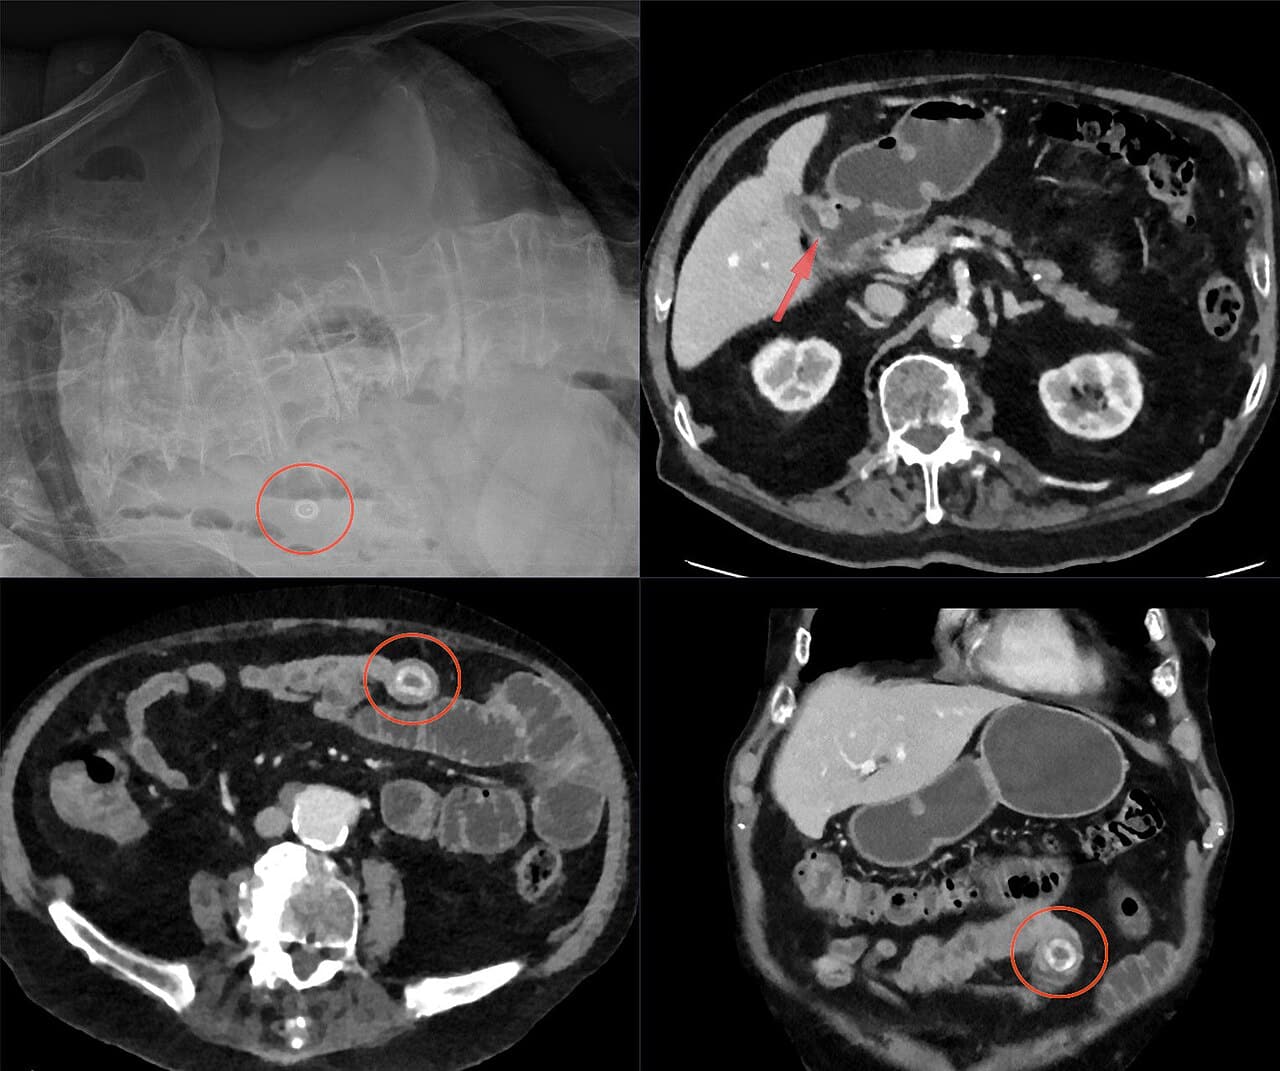

De klassieke Rigler-triade

In de medische literatuur wordt vaak de Rigler-triade genoemd. Dat is een combinatie van drie kenmerken die samen sterk wijzen op een galsteenileus:

-

Lucht in de galwegen (pneumobilie); dat gebeurt omdat de fistel een open verbinding vormt.

Tekenen van darmobstructie, zoals uitgezette darmlissen.

Een galsteen buiten de galblaas, meestal zichtbaar in het ileum.

Voor een leek klinkt dat misschien als technisch jargon, maar feitelijk gaat het om een driedelig spoor dat de radioloog helpt om de dader te identificeren.

Waarom de CT-scan de voorkeur heeft

Hoewel een gewone buikfoto soms aanwijzingen geeft, kan een CT-scan de situatie veel preciezer in kaart brengen. De CT toont de steen, de locatie waar hij klemzit, de mate van obstructie en eventuele complicaties, zoals ontstekingen of beginnende perforatie. Het is de moderne, onmisbare blik achter de schermen.

Een voorbeeld: op een CT-scan kan een radioloog exact zien dat een steen van 3,2 cm vastzit in het distale ileum, terwijl de proximale darmlissen uitgezet zijn. De combinatie van steen, lucht in de galwegen en een abnormale verbinding maakt het beeld compleet.

Differentiatie: het onderscheid met andere vormen van ileus

Niet elke obstructie is een galsteenileus; soms gaat het om adhesies (verklevingen), tumoren, ingeklemde liesbreuken of zeldzamere oorzaken. De kracht van de CT-scan is dat zij die alternatieven vrijwel altijd zichtbaar maakt. Een galsteen heeft een kenmerkende dichtheid; bovendien is de fistel vaak indirect te herkennen aan de aanwezigheid van lucht in de galwegen.

Artsen letten daarbij op subtiele patronen: de vorm van de steen, de ligging, de verhouding tussen uitgezette en normale darmlissen. Het zijn kleine details, maar zij bepalen of de diagnose scherp wordt gesteld.

Een 82-jarige vrouw wordt opgenomen met hevige buikpijn en braken. Het lichamelijk onderzoek toont een strak gespannen buik, maar nog geen duidelijke buikvliesprikkeling (peritoneale prikkeling). Op de CT-scan ziet de radioloog een steen van bijna 4 cm die vastzit in het ileum, met lucht in de galwegen en forse darmafsnoering. De conclusie is helder: galsteenileus. De operatiekamer wordt klaargemaakt; hier is geen tijd voor afwachten.